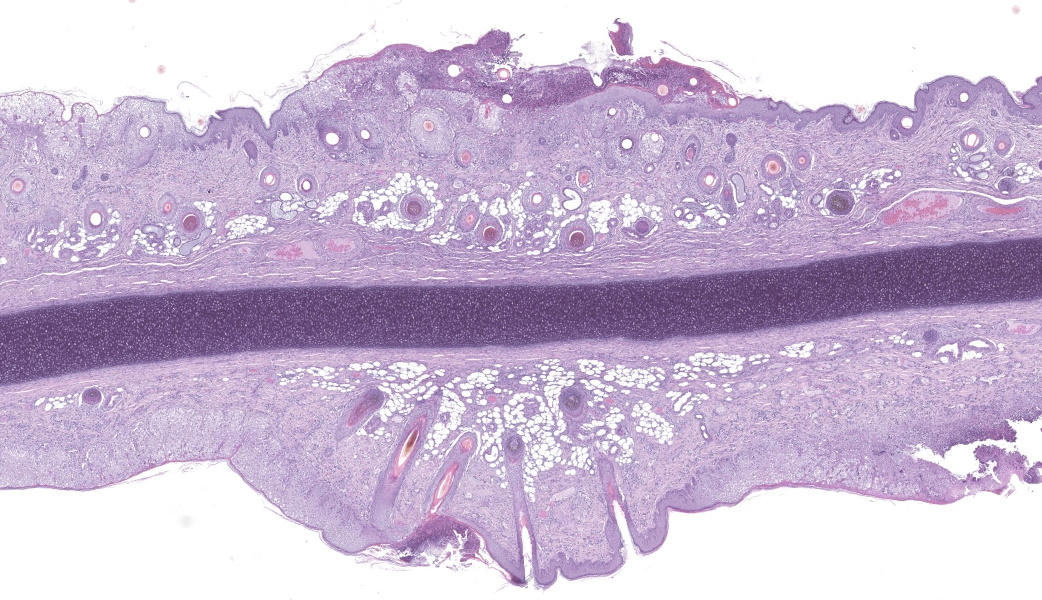

Haired skin (ear, prepuce, and inguinal area): affecting 20% of the evaluated section there is a proliferative and necrotizing process that mainly affects the epidermis. The epidermis and hair follicle epithelium show the following features: stratum corneum with diffuse mild compact hyperkeratotic orthokeratosis with multifocally serocellular crusts composed by cellular debris, degenerated keratin, degenerated neutrophils, and multiple superficial coccoid bacterial colonies (secondary contamination). Also, stratum spinosum shows multifocal marked thickening (acanthosis), and numerous keratinocytes display ballooning degeneration and intracytoplasmic perinuclear 2-5 ?m eosinophilic inclusion bodies. Multifocally, in the most affected areas, there is marked neutrophilic exocytosis, and numerous keratinocytes lost intercellular connections and undergo lytic necrosis. Superficial and mid dermis show perivascular to diffuse, moderate to severe inflammatory infiltrates composed by viable and degenerated neutrophils, macrophages, and lesser numbers of lymphocytes and plasma cells. Significant lesions were not seen in the hypodermis.Contributor's Morphologic Diagnoses:

Morphologic diagnosis: Haired skin; severe, subacute, proliferative, necrotizing, and crusting dermatitis with intracytoplasmic eosinophilic inclusion bodies. Etiologic diagnosis: Poxviral dermatitis. Etiology: Swine poxvirus.Contributor's Comment:

The typical histological features of SwPV infection comprises hydropic degeneration of keratinocytes of the epidermal stratum spinosum and follicular epithelium during the papular phase. As a result, thickening of the epidermis due to mild spongiosis can be observed; however, epidermal hyperplasia caused by SwPV is usually less prominent than that caused by the other poxviruses.7 Other finding are eosinophilic inclusion bodies in the cytoplasm of infected cells.7 Regarding inflammation, the damage caused by virus replication on keratinocytes causes recruitment of neutrophils, eosinophils, lymphocytes and histiocytes, forming intraepithelial pustules, as well as in the superficial and mid-dermis.4,6,7

Haired skin: Dermatitis, necrotizing and proliferative, subacute, multifocal, severe, with ballooning degeneration and intracytoplasmic viral inclusions.